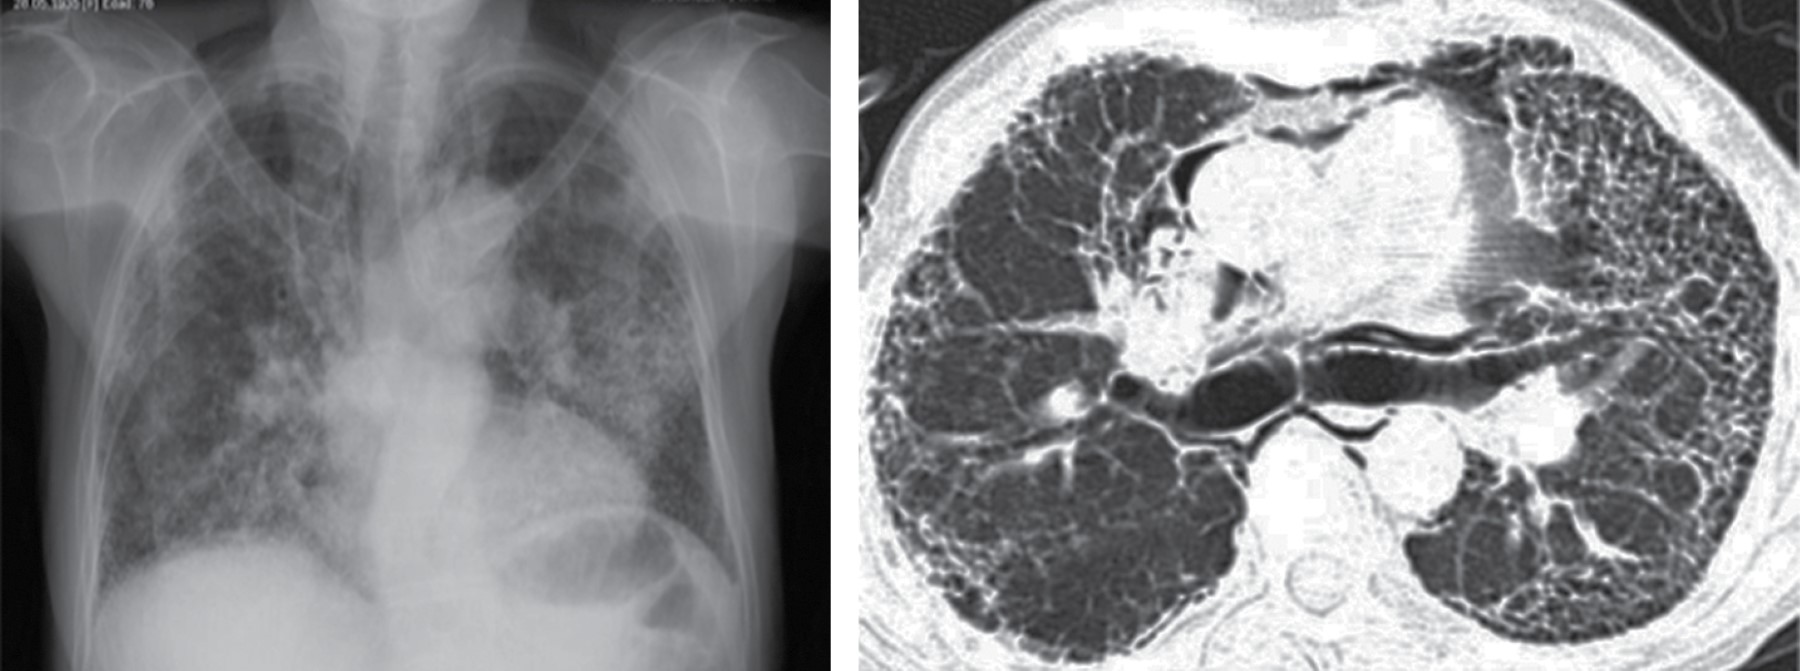

La linfadenopatía mediastinal ocurre en 7% de los adultos con tuberculosis, aunque el crecimiento de ganglios linfáticos es más común en SIDA. La linfadenopatía puede demostrar baja atenuación central, estas áreas de baja densidad dentro de los ganglios linfáticos corresponden a necrosis caseosa (Figura 1).2 La zona paratraqueal derecha es la más común, pero puede afectar el mediastino anterior o el hilio. Los ganglios linfáticos pueden coalescer en masas pobremente definidas y adherirse a las estructuras vasculares adyacentes y estructuras mediastinales.

Los hallazgos radiológicos son: ensanchamiento mediastinal generalizado en tomografía con incremento en la atenuación de la grasa mediastinal (similar a la del agua). Una masa focal no es visible. La afectación puede estar asociada con engrosamiento septal interlobular. El engrosamiento pleural o derrame pleural es visto en casi todos los pacientes (Figura 5).